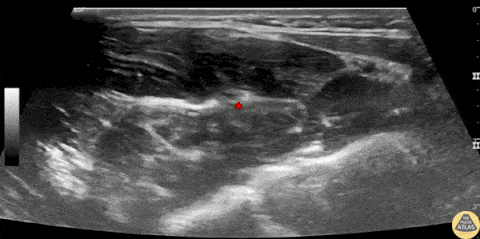

30s M presented with a unintentional laceration to the middle finger nailbed while preparing food with a knife. To provide pain control and facilitate nailbed removal and repair, a median nerve block was performed. The block is shown here, first with a survey scan of the distal volar forearm showing the median nerve (*) deep to the flexor digitorum superficialis muscle bellies and superficial to the flexor digitorum profudus muscle bellies. The nerve was anesthetized using an in-plane approach, with the needle depositing anesthetic in the fascial plane adjacent to the median nerve. The patient had improvement in his pain. He ultimately declined nailbed repair but had good pain control and was discharged with outpatient orthopedic follow up. Dr. Nimish Bhatt, Ultrasound Fellow Denver Health Ultrasound Fellowship